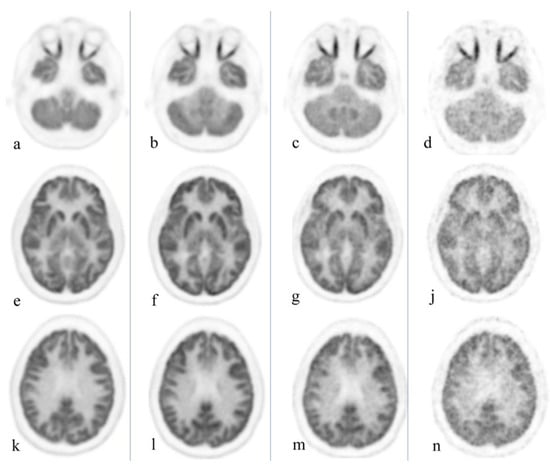

Delayed imaging further differentiates malignancy and inflammatory lesions even in FDG-avid organs such as the brain, as inflammatory changes are often characterized by early wash out [4]. Figure 3 exemplifies the substantially reduced activity associated with delayed imaging of the brain, thus ultimately enhancing detection of small/recurrent brain tumors. This differentiation between malignancy and infection/inflammation can also be achieved utilizing dual time point imaging as indicated by Zhuang et al. [20]. Moreover, this technique may potentially increase FDG sensitivity for tumor detection, thus providing the geographic tumor distribution and quantification of microscopic deposits throughout the body, information vital for ultra-staging and management decisions [21].

Figure 3.

Healthy volunteer, total body PET/CT 20-min acquisition at 40 min, 3 h, 6 h, and 9 h after administration of 10 mCi of 18F-FGD. Cuts were selected at the orbit level (a–d), basal ganglia (e–j), and upper aspect of the ventricles (k–n). Brain uptake slowly decreases over time; the increase in noise level starts to become clinically evident at 9 h. Reprinted with permission from Ref. [4]. Copyright 2020 Elsevier.